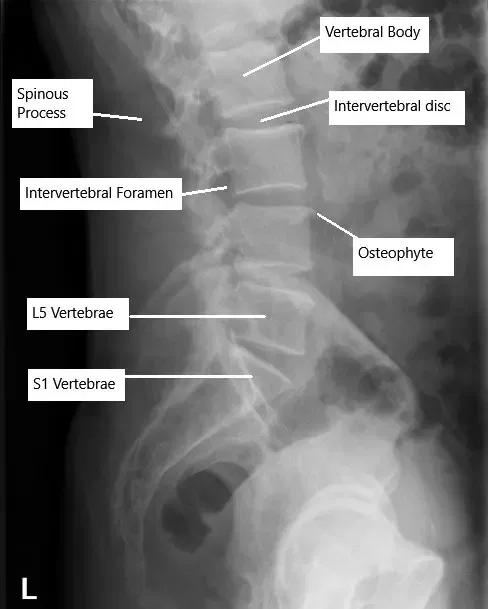

X-ray of the lumbar spine showing degenerative changes.